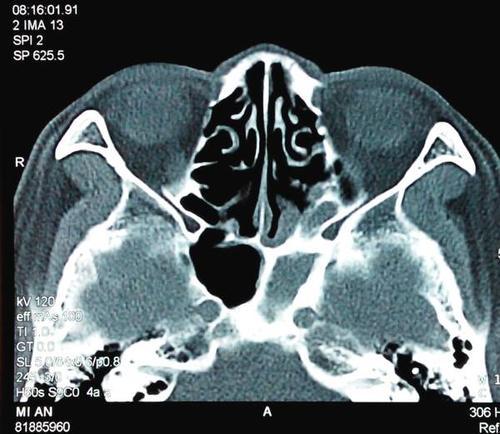

蝶窦CT

鼻窦ct解剖图

蝶窦ct解剖图